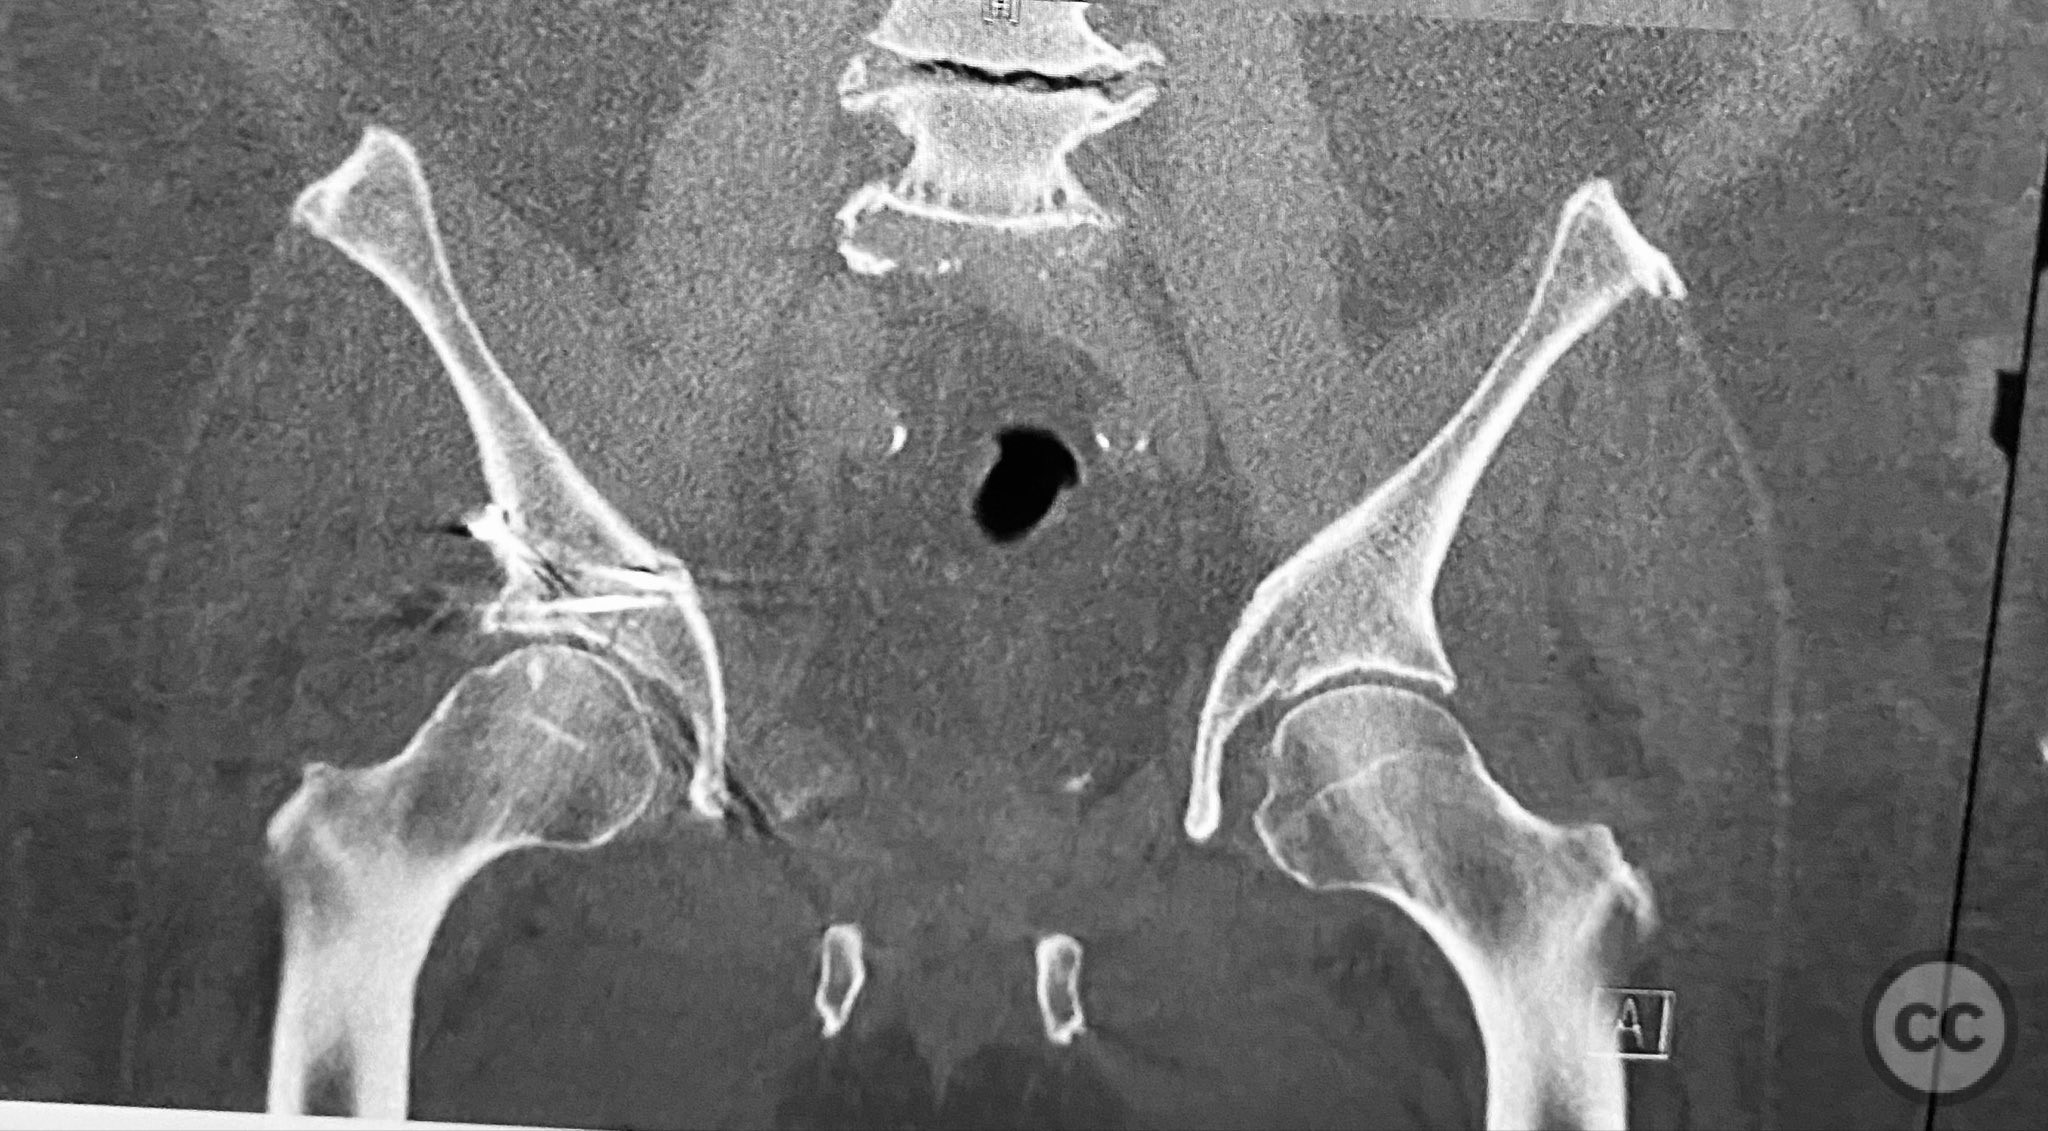

Clinical and radiological findings:  A 79-year-old male sustained a high-energy injury in a motor vehicle collision, resulting in a complex acetabular fracture-dislocation. Radiographs and computed tomography demonstrated a posterior wall and transverse acetabular fracture (AO/OTA 62-B1.3), with the posterior wall fragments displaying an atypical caudal hinge configuration. The medial wall fragment was non-articular. Axial imaging revealed an impacted osteochondral fragment obstructing reduction, as well as disruption of the capsular structures adjacent to the intact articular segment. The obturator internus tendon appeared taut but intact, with no evidence of sciatic nerve impingement or superior gluteal neurovascular compromise.

Planning remarks:  The preoperative plan included open reduction and internal fixation via a Kocher-Langenbeck approach in the prone position. The strategy entailed removal of the impacted intra-articular fragment, anatomic reduction and provisional fixation of the transverse component, reduction and fixation of the posterior wall, bone grafting and reduction of the impacted articular segment via the medial wall window, and definitive fixation of the medial wall. Capsular repair was planned prior to closure.